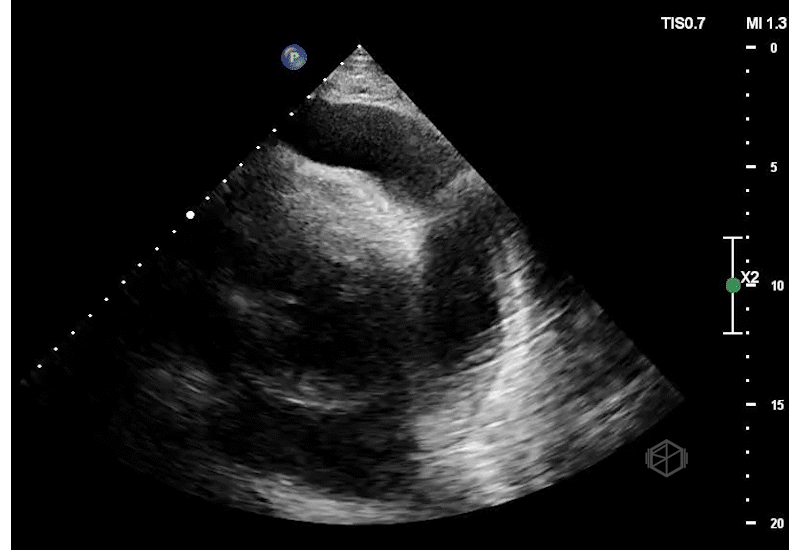

They did a POCUS echo and saw the following —

Not just rapid atrial fibrillation!

This is a massive pericardial effusion, measuring up to 5.0cm in it’s largest portion. There are signs of tamponade on this echo — aside from the obvious “swinging heart,” there is right ventricular diastolic collapse. The right ventricle does not get a chance to fully fill during diastole due to the extra-cardiac pressure from the pericardial effusion.

Diagnosis: Extra-large pericardial effusion with a side of tamponade

The patient had 1500ml of serosanguinous fluid drained by cardiology.